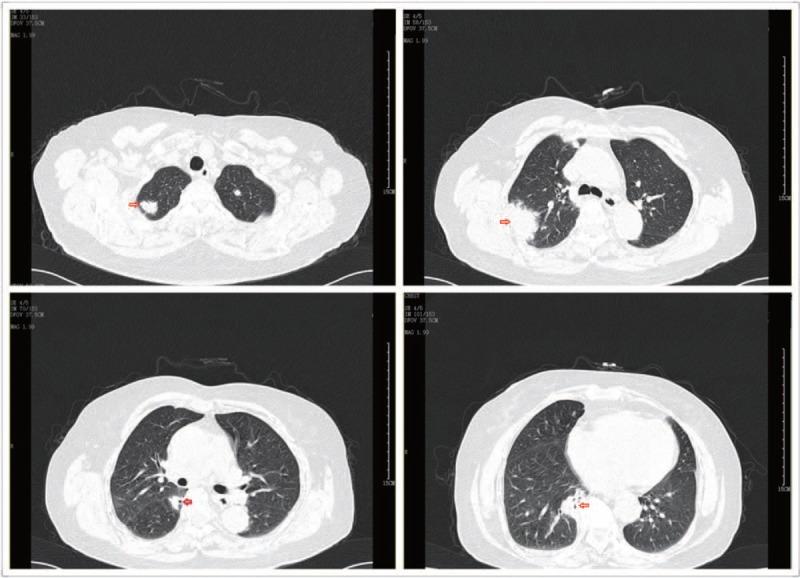

Chest high-resolution computed tomography (HRCT) revealed multiple nodules, masses, and cavities. Urinalysis indicated microscopic hematuria. Test of proteinase3-anti-neutrophil cytoplasmic autoantibody (PR3-ANCA) was positive.

胸部高分辨率计算机断层扫描(HRCT)显示多个结节、肿块和空洞。尿液分析显示镜下血尿。蛋白酶3抗中性粒细胞胞浆自身抗体(PR3-ANCA)检测呈阳性。